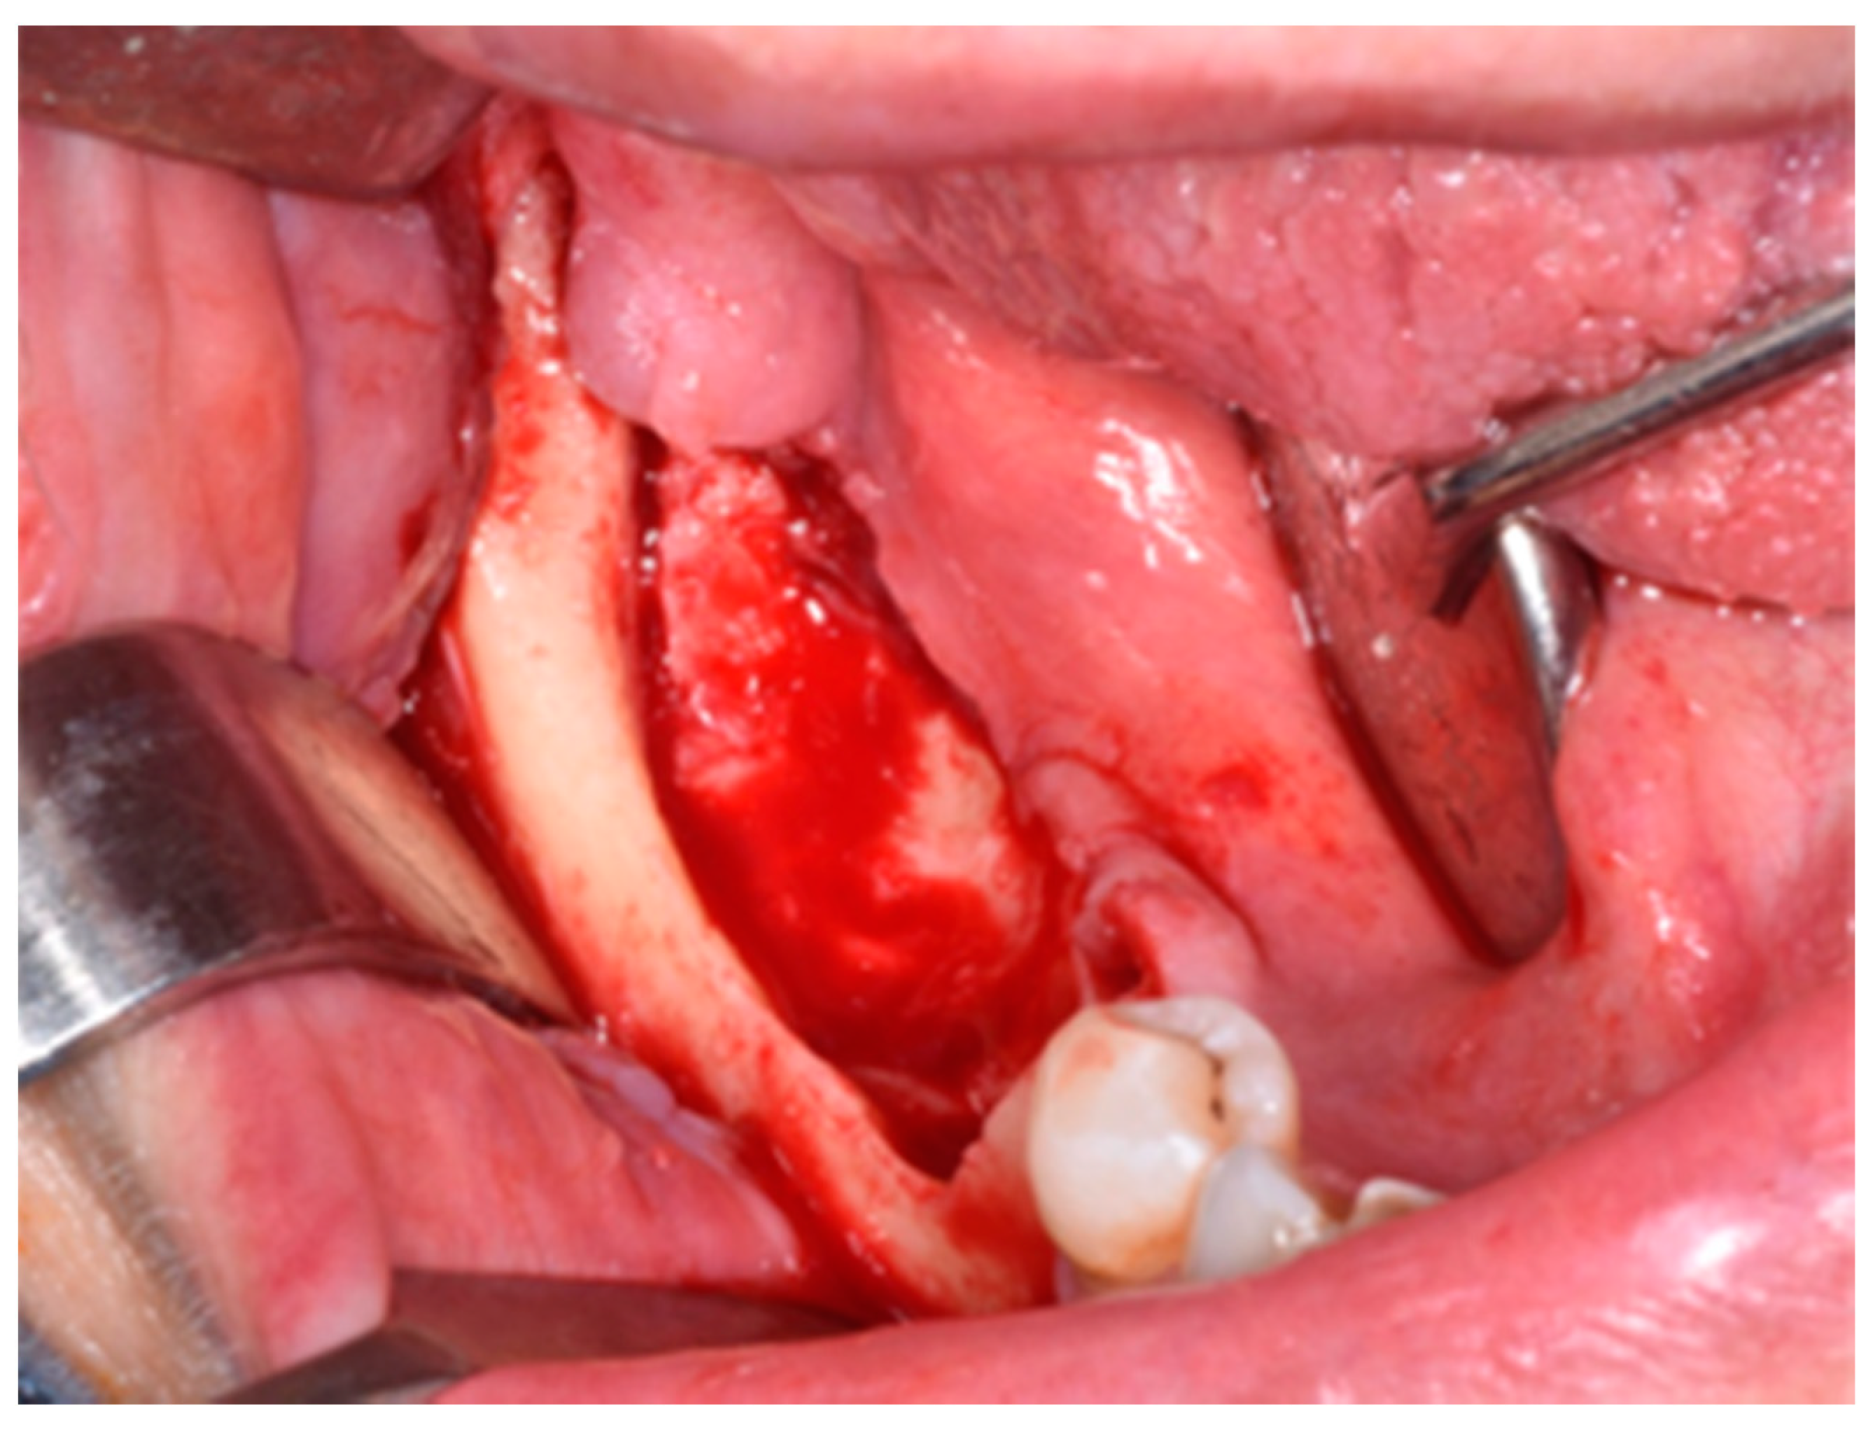

2. Materials and Methods

3. Results

4. Discussion